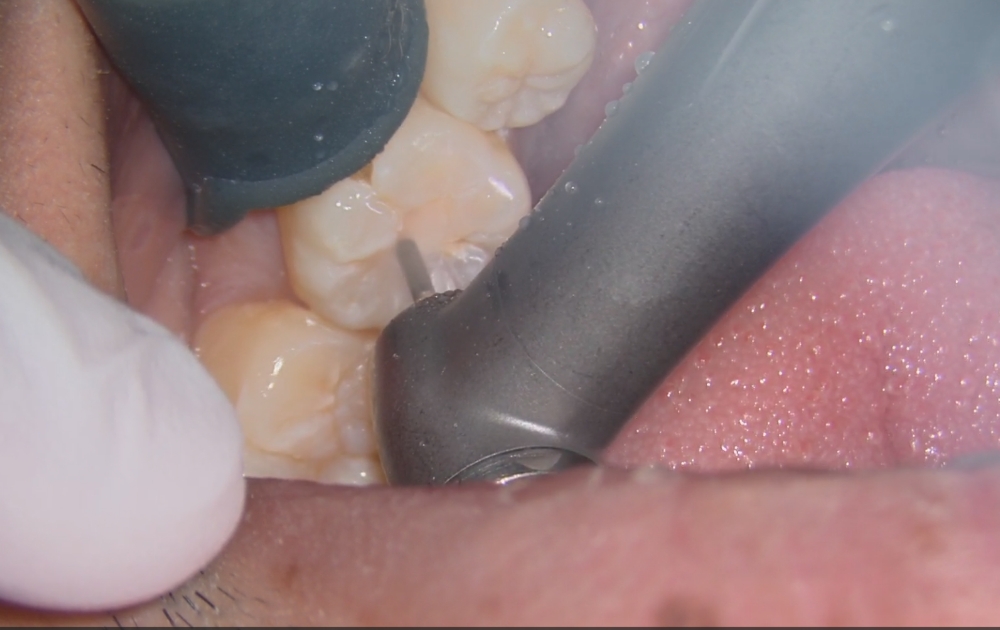

• 3.噛み合わせの面にある古いプラスチック(レジン)を外していきます。過去の治療部分を丁寧に取り除き、内部の状態を確認します。

3.噛み合わせの面にある古いプラスチック(レジン)を外していきます。

過去の治療部分を丁寧に取り除き、内部の状態を確認します。